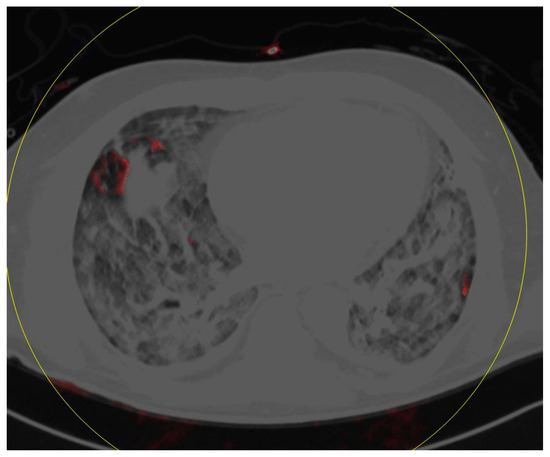

Dual-Energy Computed Tomography of the Lung in COVID-19 Patients: Mismatch of Perfusion Defects and Pulmonary Opacities